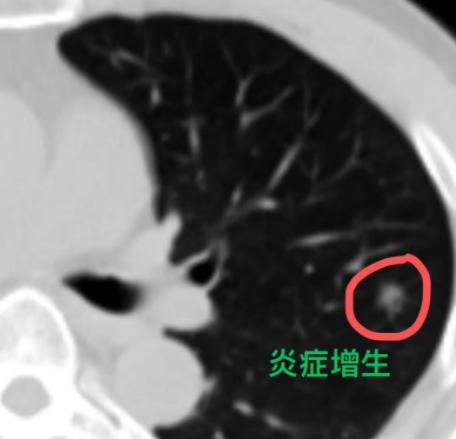

朋友们!别一看到“肺结节”几个字就紧张!其实在检查中发现肺结节非常普遍,绝大多数都和炎症有关,真正由肿瘤引起的情况极少。 肺结节本身是一个影像上的描述,不代表就是不好的东西。所以查出肺结节后,先别急着做手术,不妨给自己一点观察的时间。 一般来说,肺结节可能有以下几种情况: 1、急性炎症引起的结节,可以用消炎药。比如最近正好有发烧、咳嗽,同时查出了肺结节,这很可能是呼吸道感染导致的。 按照医生建议吃一段时间的消炎药,把细菌控制住,结节很可能就慢慢消失了。 这种炎症期的结节,在CT上常常表现为边缘模糊、不太规则,有时候像一小片云雾。 2、有些炎症结节,不用药也可能自己消失。当我们免疫力下降,或者接触的细菌比较多时,肺部可能出现局部炎症。 但如果注意休息、提高抵抗力,身体里的免疫细胞是有能力把这些细菌清除掉的,结节也就随之消散了。 3、还有一些结节是炎症吸收后留下的“痕迹”,就像皮肤受伤后结的疤,已经稳定了。这种陈旧性结节,吃消炎药通常也消不掉,重点就不是用药,而是定期复查、观察变化。 所以,查出肺结节先别慌,大多数情况下它并不可怕。平时注意保持健康生活习惯——吃好、睡好、心情放松,让免疫力维持在良好状态,就是对我们肺最好的保护。[玫瑰][谢谢]胸外科乔贵宾医生肺结节[超话]